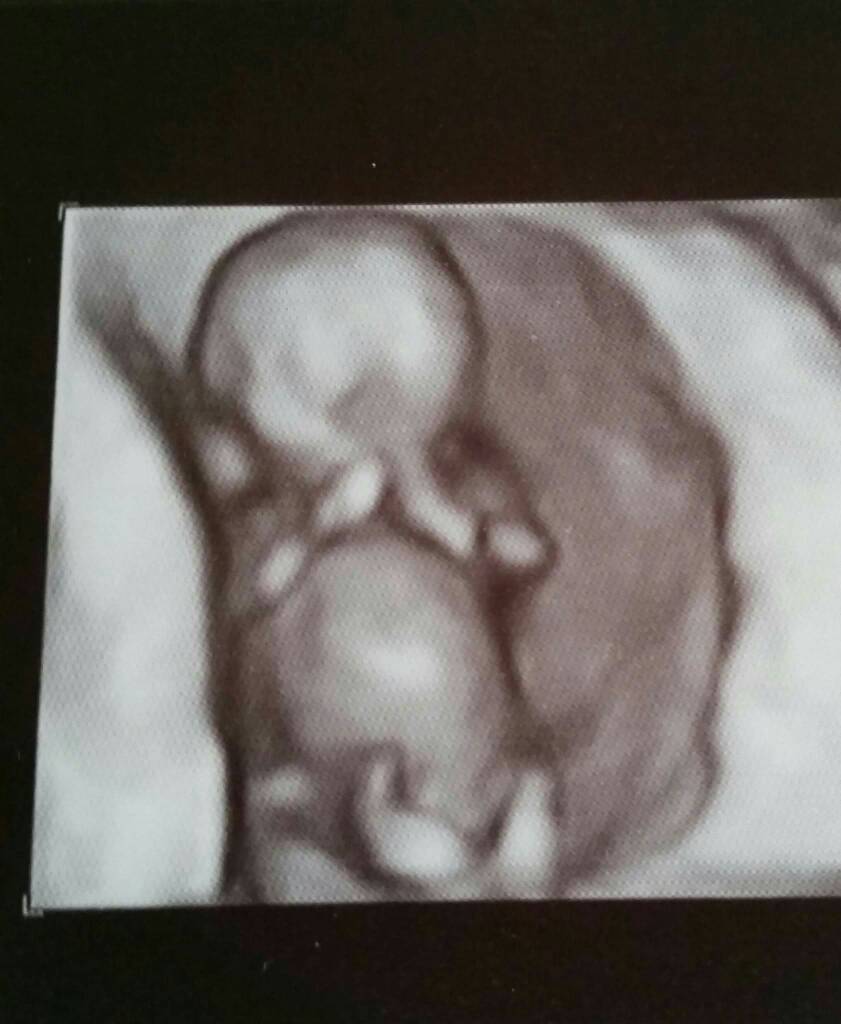

Super, gratulacje. To mam Ci tego chłopca już na liście wpisać?To ja też po wizycie. Udało się zrobić od razu usg genetyczne. Na 70% chłopak!!! Ale fajnie się trafilo - córka za 2 tyg roczek skończy także będą jak bliźniaki hehe Zobacz załącznik 760633